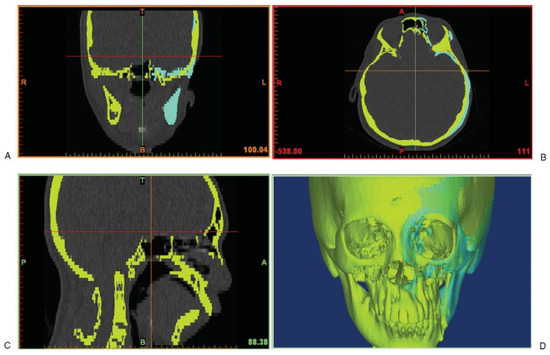

The CT scan images of the patient’s skeleton in Digital Imaging and Communications in Medicine (DICOM) file format were imported into medical image processing software called Mimics v13.0 (Materialise, Leuven, Belgium). The CT data were then converted to a mask of the deformed facial skeleton created using thresholding technique with default setting of Hounsfield units (Figure 1). Different algorithms such as thresholding, mathematical morphology, and region growing and smoothing techniques were utilized to automatically segment the skull bone in the CT data. However, the noise or unwanted pixels, which were still connected with the facial skeleton due to low resolution of the CT scan, were difficult to be isolated. Therefore, manual subtraction of the noise pixels under the supervision of the surgeon was carried out to further segment the facial skeleton, and eventually the 3-D model of the original distorted facial skeleton was reconstructed (Figure 1).

The mirroring was done in HyperMesh v10.0 (Altair HyperWorks, Troy, MI, USA) whereby the model of the normal right half was imported as stereolithography (STL) format and then reflected to the left-hand side (Figure 1). Following the mirroring, the meshes of reflected left facial skeleton were imported back into Mimics in STL format to generate the mask of the reflected left half. As such, this reverse engineering method enabled us to reconstruct a 3-D model of a selected skull. In this case, the reflected facial skeleton on the patient’s left side was reflected from the normal right half of the skull.

Figure 1. Computed tomography data with the yellow mask showing the original distorted facial skeleton and the cyan mask showing the reflected left skull from the healthy right half.